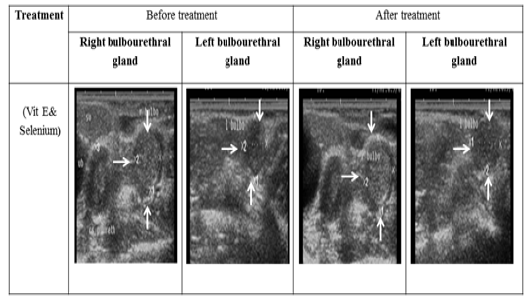

Ultrasonographic image of ram’s bulbourethral glands treated with vit E and selenium. The length and breadth of bulbourethral glands increased after vit E and selenium injection.